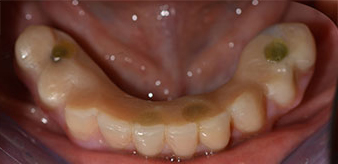

Пациентката е 64-годишна жена с частично обеззъбяване на зъби 38, 33 и 43 и частична долночелюстна протеза (Фиг. 1 и 2).

частично обеззъбяване

Фиг. 1

Фиг. 2